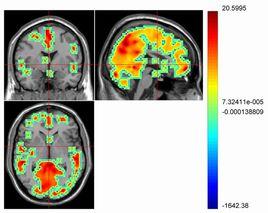

EPI最大的優點在於它作為一種多層成像技術時可在高解析度的前提下對全腦進行定位。比如,大約5s就可得到一個解析度在三個方向上均為3mm的64×64×64的圖像矩陣。每層的TR為5s,在fMRI場強條件下組織和血液中的T1為1s的數量級,飽和效應很小。而且,EPI及其派生技術(如Single-Shot GRASE,Single-Shot Spiral EPI)的獲取信息率(即單位時間的信噪比)最高。圖2所示對短暫視覺刺激時fMRI時間序列。

統計參數映射(SPM)和fMRI獲取方法的研究推動了事件相關fMRI的發展。事件相關fMRI是研究對單一事件的局部腦血流動力學反應。事件和一定的規則相結合,觀察在不同時間段對應不同事件的皮層區域的情況。此外,fMRI的非介入性質使它可作為一種理想手段來研究未知事件,即受試者只有在事件發生時才產生反應信號。圖3所示為光刺激事件的fMRI圖像。